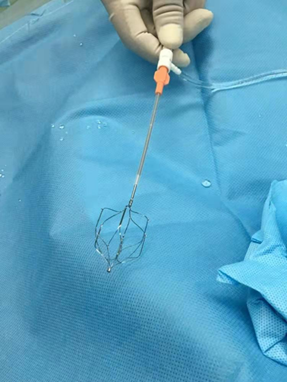

下腔静脉置入术指的是通过股静脉或者颈静脉进行穿刺,插入静脉导管,然后把特殊的过滤器放置到下腔静脉,用来过滤通过下腔的脱落血栓,主要用于下腔静脉血栓、髂静脉血栓和下肢深静脉血栓等疾病治疗,可以防止血栓进入心脏,造成肺动脉栓塞等不良后果。

下腔静脉滤器是为预防下腔静脉系统血栓脱落引起肺动脉栓塞而设计的一种装置。主要适用于以下患者: